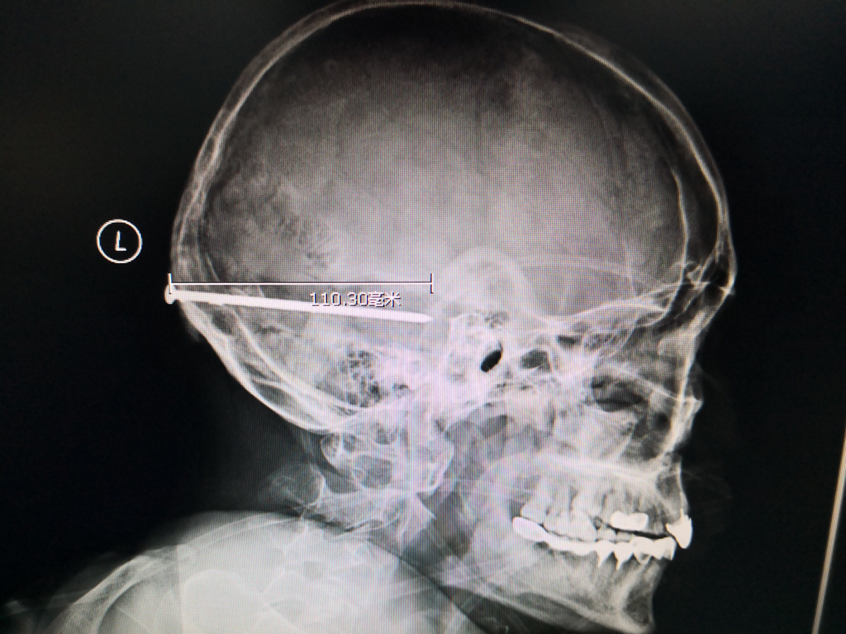

28日晚上11点,郑先生通过急诊住进了同济医院神经外科,神经外科张所军教授立即组织会诊。张教授介绍,钢钉12厘米长,从枕部刺入颅内,伤及小脑、矢状窦,尖端逼近脑干。钢钉穿透颅骨和硬脑膜,大部分位于脑组织内,还好钉尾卡在了头骨上使其固定住。否则钢钉射穿头骨,处于“游走的状态”,哪怕是轻轻晃动脑袋,郑先生都可能会发生二次伤害,如果伤及脑干,那便“无力回天”。

12厘米长钉刺入脑内 同济医生紧急开颅取钉